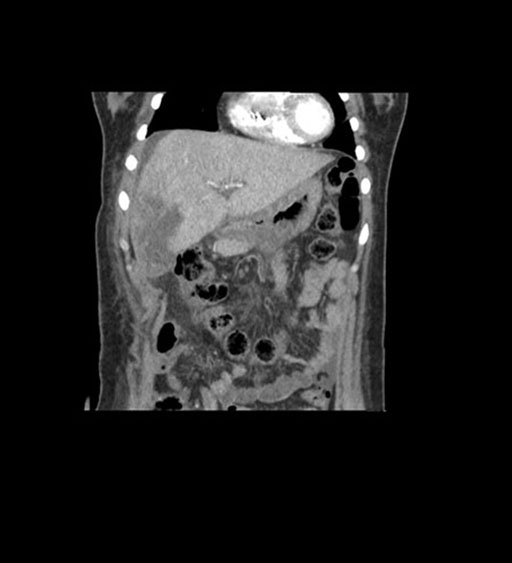

Coronal Arterial

Coronal Venous